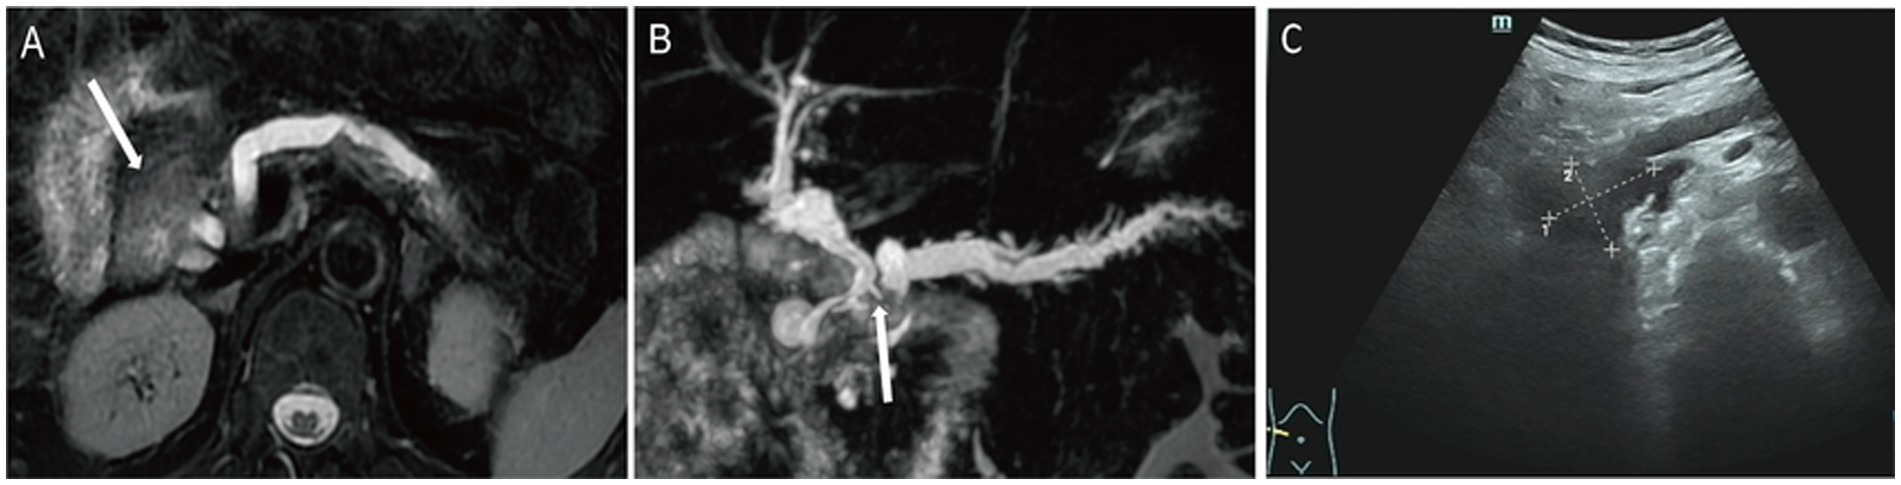

T2WI demonstrated a mildly hyperintense lesion in the pancreatic head with internal hypo-intense septations and significant dilation of the upstream pancreatic duct (Figure 3A). The lesion was hyper-intense on DWI (Supplementary Figure 4A) and iso-intense to muscle on the ADC map. Post-contrast imaging showed progressive moderate enhancement of the lesion, with enhancement intensity less than that of the normal pancreatic parenchyma (Supplementary Figure 4B). MRCP reconstruction revealed a tumor located within the main pancreatic duct of the pancreatic head, accompanied by significant dilation of the upstream pancreatic duct and compression of the common bile duct (Figure 3B), raising suspicion for a malignant neoplasm of the pancreatic head. The patient underwent pancreaticoduodenectomy. US showed that an anechoic mass was seen in the pancreatic head, communicating with the pancreatic duct (Figure 3C).

Figure 3

Case 3: axial T2WI (A) demonstrated a slightly hyperintense lesion in the pancreatic head, containing internal hypointense septation. On MRCP reconstruction (B), a tumor localized within the main pancreatic duct of the pancreatic head, with marked upstream pancreatic ductal dilation and compression of the common bile duct (white arrow). On US, an anechoic mass (C) was seen in the pancreatic head, which communicates with the pancreatic duct.